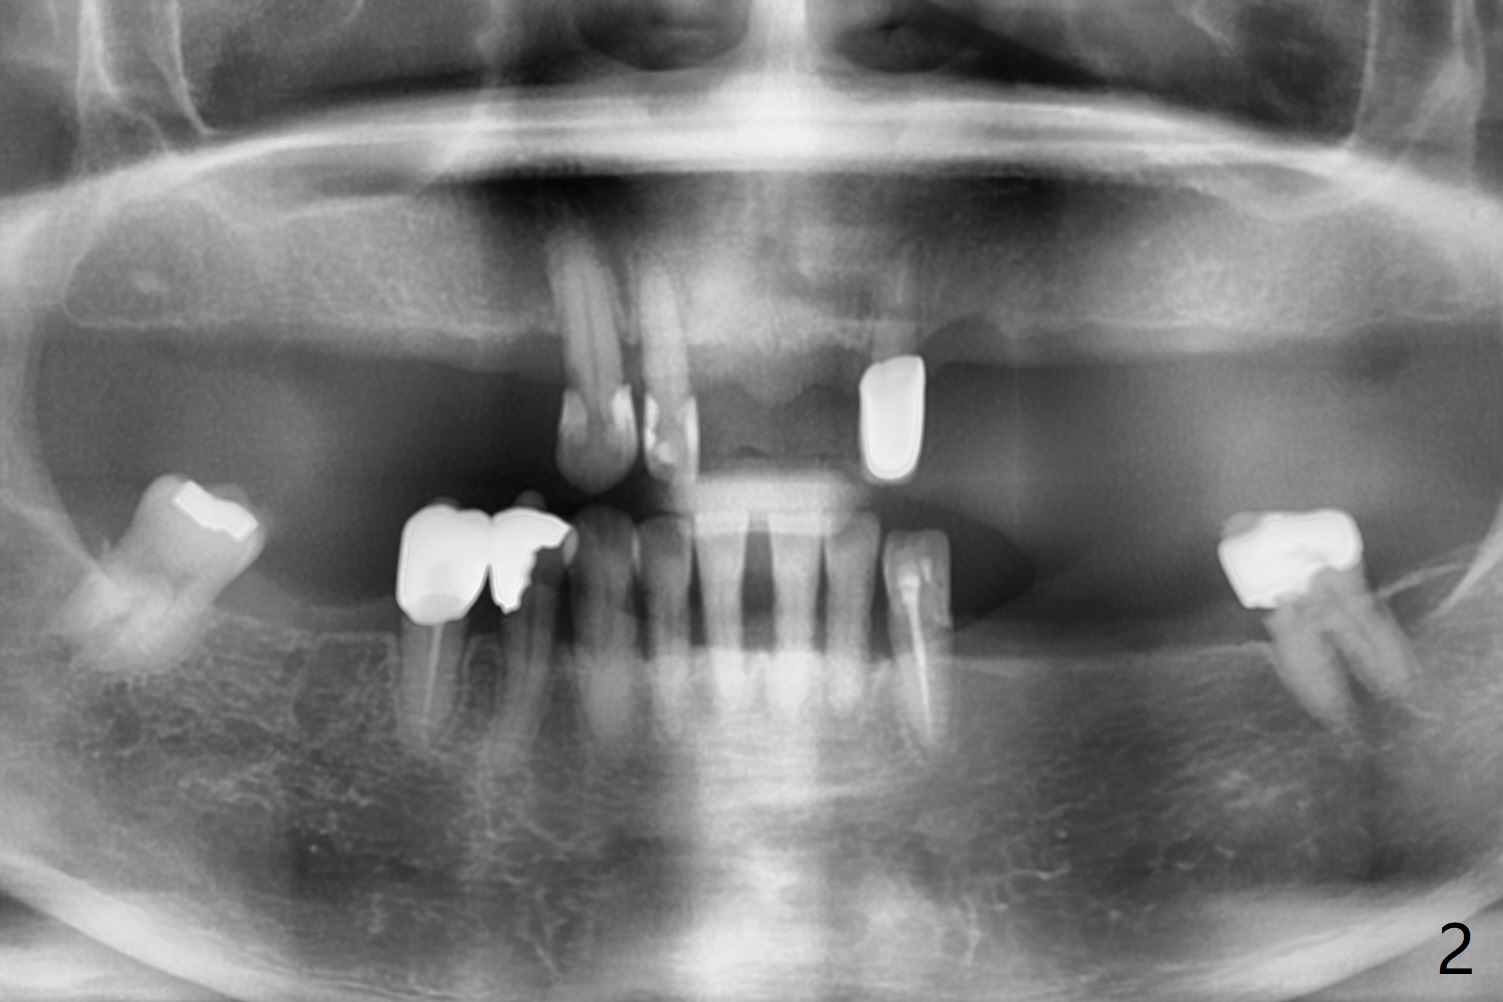

A 64-year-old woman with partial edentulism requests an implant for #30 after #29 crown temp bond cementation (Fig.1). The buccal, crestal and lingual cortex is equally thin (no deviation). The medulla is porous. The average bone density is 600 units. Ask the patient about osteoporosis treatment. A 4.5x10 mm implant with deep placement is going to have 2 mm bone buccal and lingual. Underprep is necessary (the last drill 3.5x10 mm). Due to metal scattering from amalgam from #28,29,31, a larger field view of CT is taken (Fig.2). Although the cancellous bone looks porous (Fig.3), the average bone density is 1000 units. The 2nd analysis shows that the ridge is narrower, allowing safe placement of a 4 mm implant (Fig.4,5). In spite of keratinized gingiva in the edentulous area, incision will be made to make sure the ridge top is being flattened by bone trimmer. If it is insufficient, use rotary instruments.